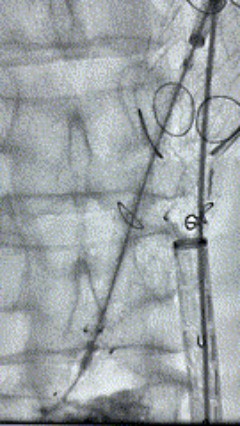

8. 从右侧股动脉入路送入腹主支架AB-24-12-110-S,近端重叠胸腹主动脉支架远端,调整好支架位置后释放。

9. 经左股动脉送入导丝导管,超选进腹主动脉支架短腿内,后沿导丝送入髂支,同理,右侧沿导丝送入髂支并释放,使用J9集团国际顺应性球囊后扩各支架连接处及支架近远端,最后通过预留导管向瘤腔注入人纤维蛋白粘合剂数支,造影显示分支通畅。